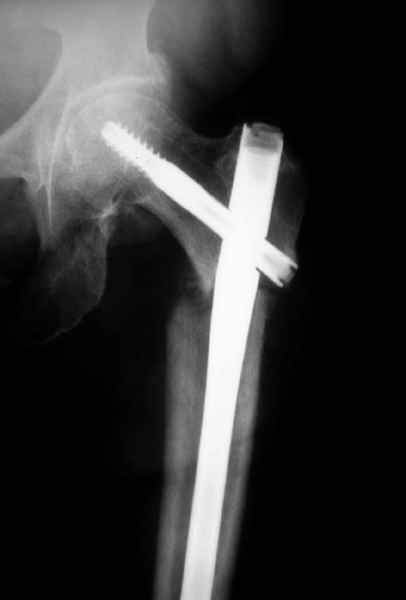

77 летняя больная направлена в нашу клинику на дальнейшее лечение. Из истории, травму получила в сентябре 2007 года и по поводу перелома шейки бедра больная была проперирована тремя каннюлированными шурупами с явным нарушением технологии установки шурупов. Внизу вместо одного шурупа имеется два, что привело к стрессу латерального кортекса. Через месяц по поводу ятрогенного подвертельного перелома сделана фиксация длинной Гамма 3. Установлен без проксимальной блокировки? (set screw). В данный момент имеется несостоятельность конструкции и ложный сустав. Передвигается с помошью костылей, конечность укорочена на 2 см. Какие будут рекомендации?Djoldas Kuldjanov, MDDepartment of Orthopedic SurgerySt. Louis University Medical Center

Михаил, здравствуйте. Если присмотреться - на четвертом снимке есть перелом гвоздя по отверстию.

Видимо, проблем тут две: во-1-х, центральный отломок был оставлен в варусно-сгибательной установке, во-2-х, не динамизировали вовремя.

Нижние винты хотели сломаться, но, увы, один не сломался, и тогда сломался гвоздь. Хотя и при динамизации в таком положении отломков

могло не срастись.